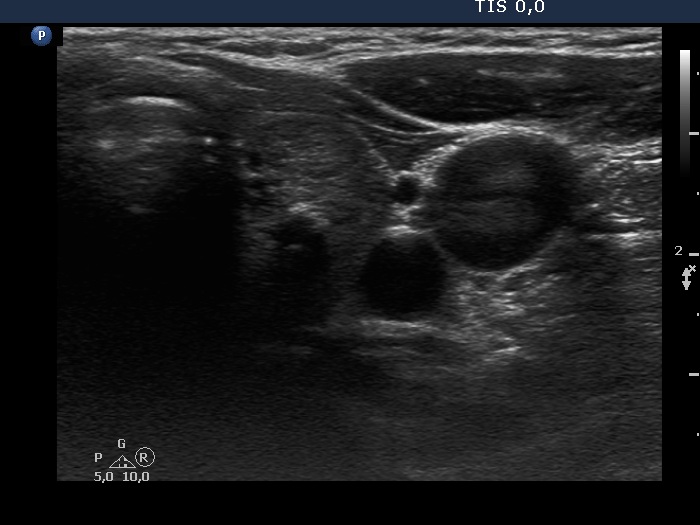

The echogenicity of the nodule - case 1782 (ultrasonographic picture 5)

Left lobe, transverse scan.